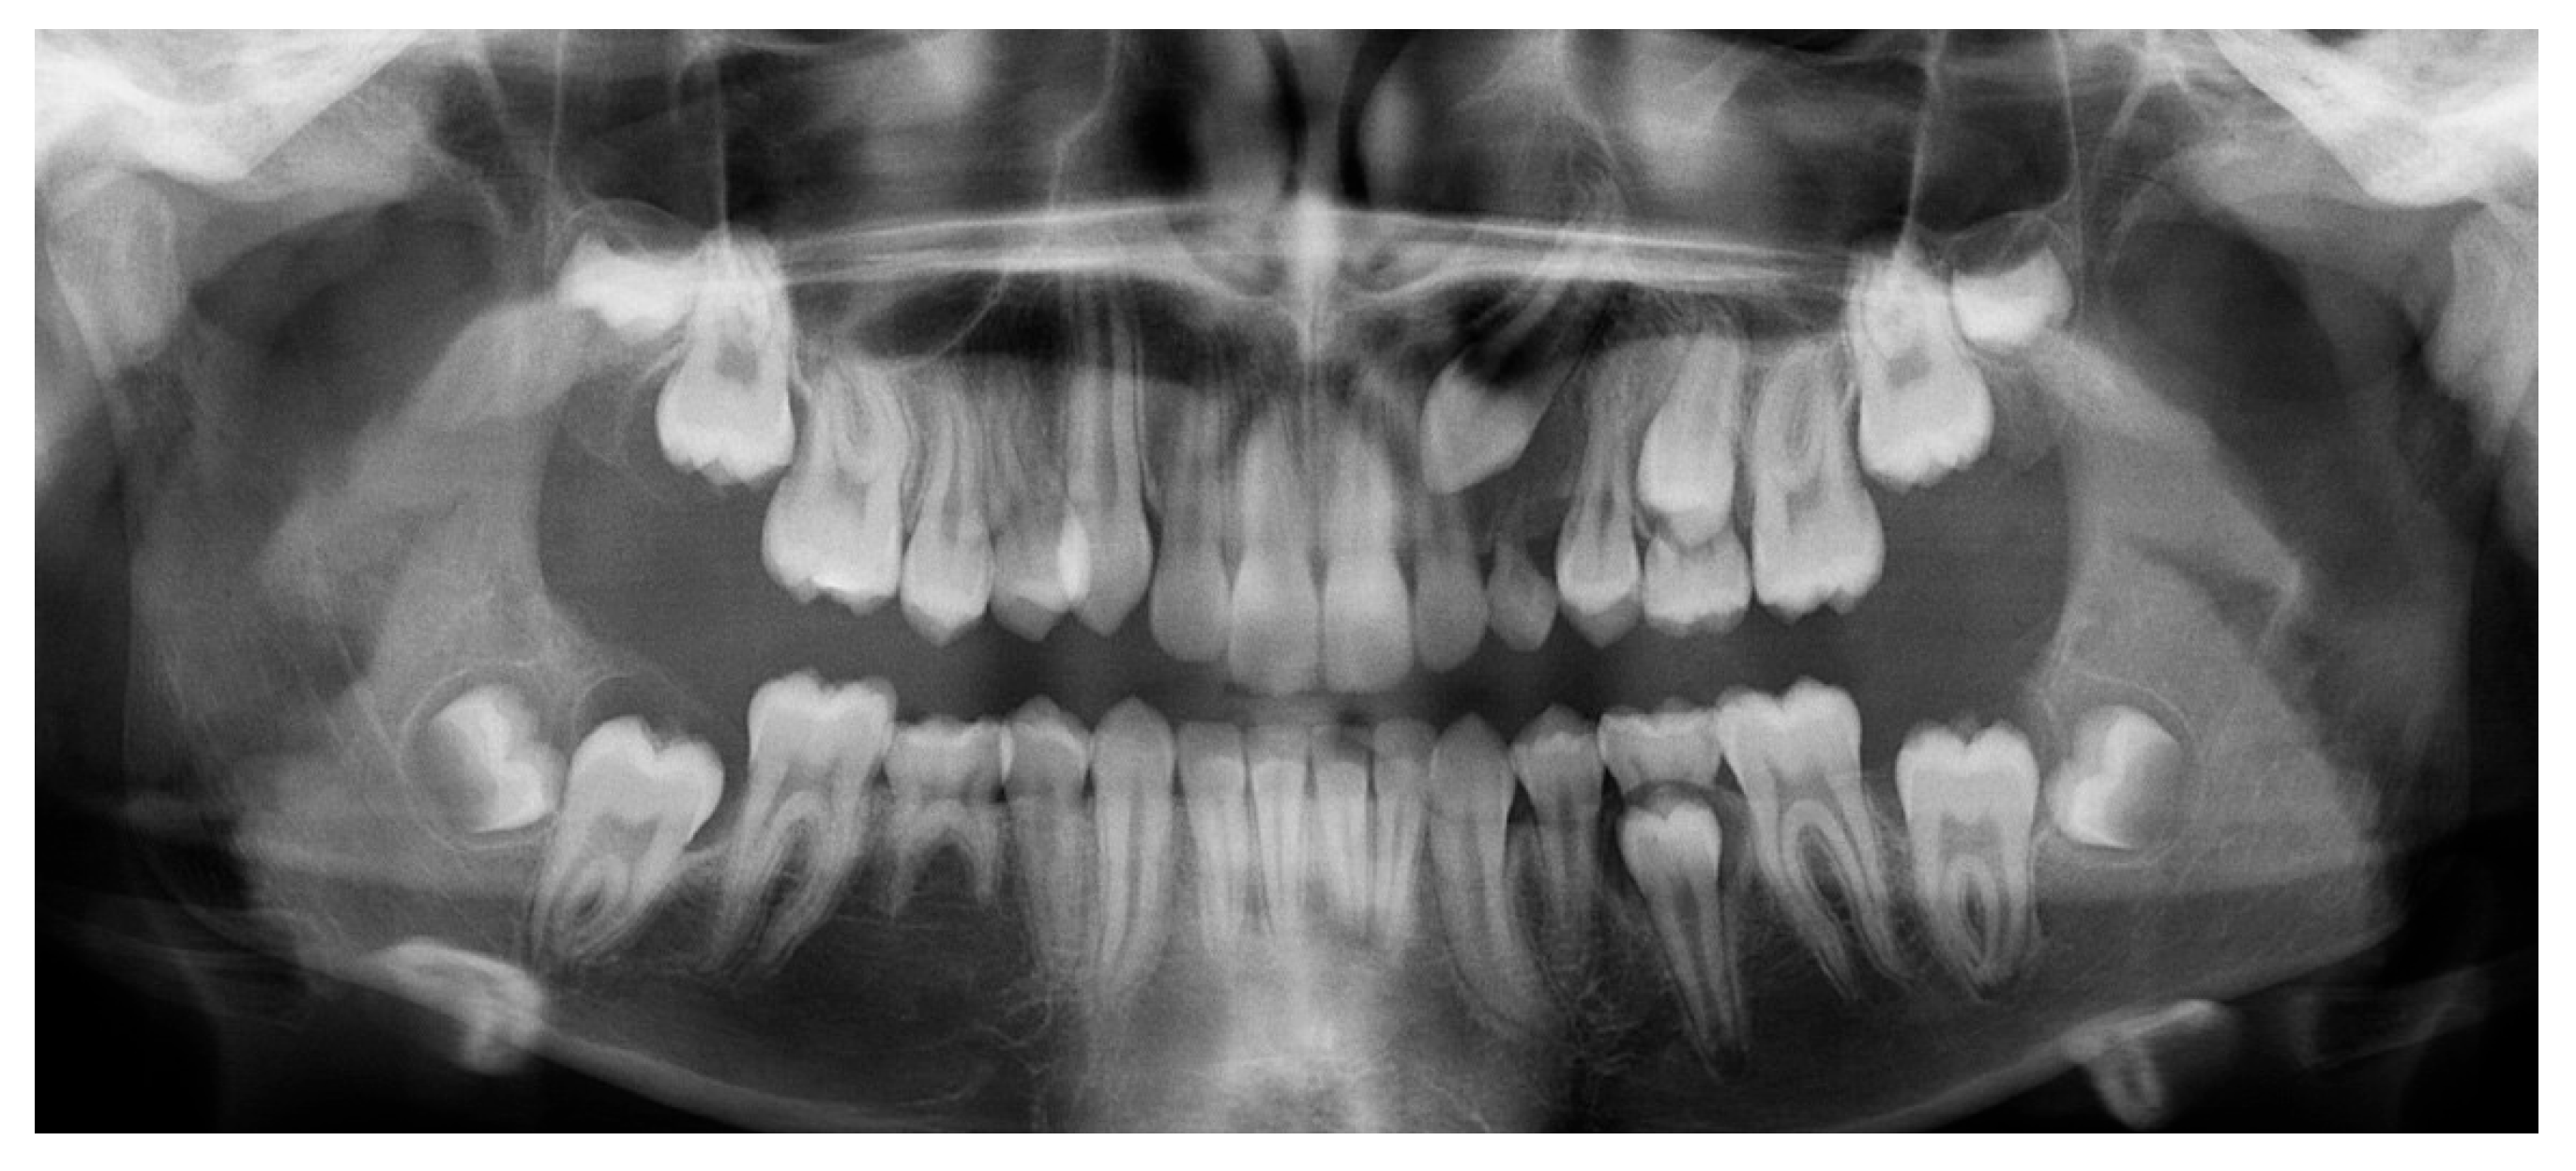

A 13-year-old male patient presented with Class II Division 2 malocclusion, a bilateral Class II sagittal relationship, and retroclined incisors. Cone-beam computed tomography revealed a palatally impacted maxillary left canine (tooth 23), with its cusp located palatally to the apical half of the left lateral incisor. The root exhibited significant apical curvature, extending toward the floor of the maxillary sinus (Figure 12 and Figure 13), making spontaneous eruption unlikely.

Figure 12.

Initial intraoral lateral photo.

Figure 13.

Impacted canine 23 with its cusp palatally positioned to the apical half of the left lateral incisor, with the root significantly curved and inserted into the maxillary sinus.